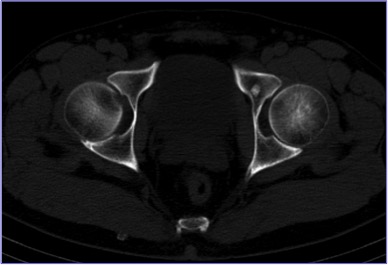

Types of tests: planar bone scintigraphy, SPECT/CT of the skeleton.

Aim: to visualize abnormalities of the skeleton (local areas of metabolic dysfunction of bone tissue).

Nuances: bone scintigraphy is a high-sensitivity / low specificity test. In some instances, osteochondrosis, arthrosis and changes of the skeleton caused by trauma may lead to an erroneous conclusion. In this case, it is recommended to perform SPECT/CT. The use of Tc-99m-labeled bisphosphonates increases the sensitivity of the test.

SPECT/CT of the skeleton allows a better assessment of the condition of the skeleton if the results of bone scintigraphy are inconclusive. It helps to identify metastases that are 5-10 mm in size. It is a reliable technique for evaluating the efficacy of treatment of metastases with bisphosphonates and chemotherapeutic agents. SPECT/CT is recommended for patients with primary cancer of the prostate and breast, kidney and urinary bladder cancer, lung cancer (if PET/CT cannot be performed), melanoma, histiocytosis, malignant neoplasms of the gastrointestinal tract and reproductive system, embryonal tumor and osteosarcoma.